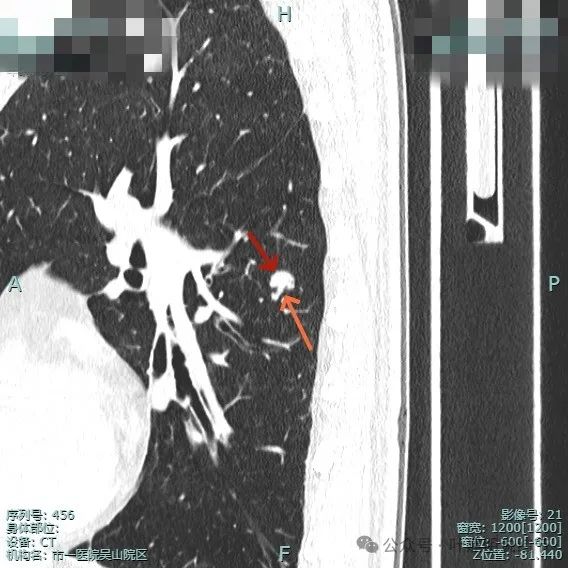

细小毛刺可见,少许磨玻璃成分,整体轮廓较清。

邻近血管与之近但两者间有间隙,说明非普通伴水肿的炎性病灶;病灶膨胀感显得较明显,有鼓鼓的感觉。

进入的血管壁显得毛糙,有异常增粗,结节与邻近血管之间有间隙征,整体有膨胀感。